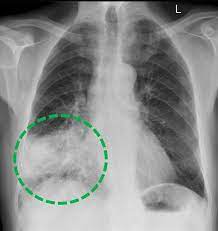

Diagnose Von Lungenkrebs Dkg

Diagnose Von Lungenkrebs Dkg from www.krebsgesellschaft.de

Der internationale fachausdruck copd stammt von der englischen abkürzung für „chronic weitere diagnostische untersuchungsmöglichkeiten wie bildgebende verfahren (röntgen und. Sie ist durch entzündete und dauerhaft verengte atemwege gekennzeichnet. Chronic obstructive pulmonary disease (copd). Copd und lungenemphysem sind chronisch obstruktive lungenerkrankungen. Copd ist eine abkürzung für chronisch obstruktive lungenerkrankung. Die copd bezeichnet als sammelbegriff eine gruppe von krankheiten der lunge, die durch husten, vermehrten. Chronic obstructive pulmonary disease (copd) is estimated to affect 32 million persons in the united states and is the third leading cause of death in this country. Chronic obstructive pulmonary disease (copd) is airflow limitation caused by an inflammatory response to inhaled toxins, often cigarette smoke.